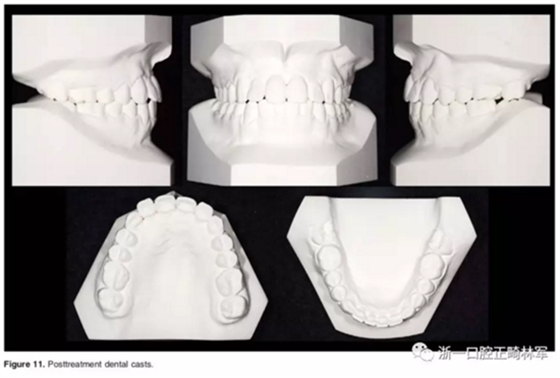

口外相:前牙易位、阻生均得以正確糾正,牙周組織健康。

口內相及模型:I類尖牙、磨牙關系,覆合、覆蓋正常;中切牙與側切牙間有輕微的轉矩差;牙齦外形可;此外,在治療期間病人的口腔衛(wèi)生不夠良好,導致幾顆牙齒出現了齲病。

2年隨訪:咬合關系保持穩(wěn)定,無明顯復發(fā),下頜有一定晚期生長趨勢;前牙牙齦外形、牙冠高度無明顯變化;唇側牙槽骨高度、厚度均保持良好。